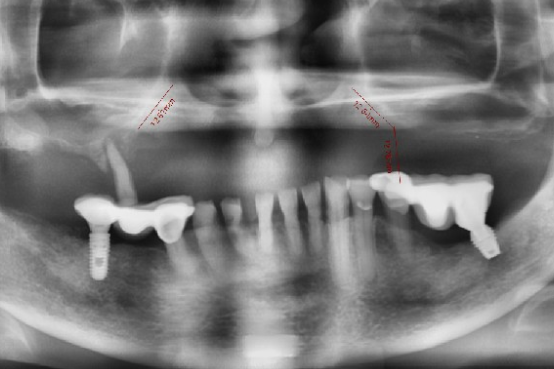

微創植牙手術是什麼?誰適合?一次看微創植牙療程、優勢及風險!

微創植牙是一項先進的牙科治療技術,為那些缺牙問題困擾的人提供了一個可靠且持久的解決方案。無論是因為意外事故、牙齒腐爛或是其他因素導致的牙齒損失,植牙都能恢復您的自信笑容和咀嚼功能。